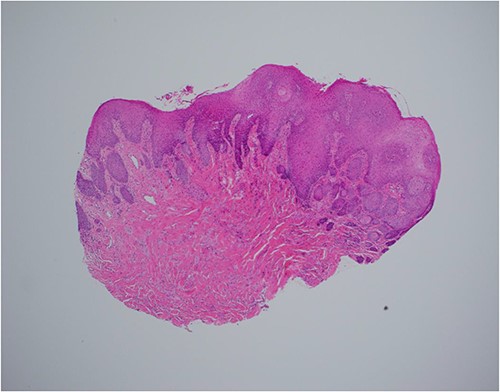

Haematoxylin and eosin stain, 40× magnification, showing reactive epithelial hyperplasia on the surface, this can be mistaken for squamous cell carcinoma in a superficial biopsy.